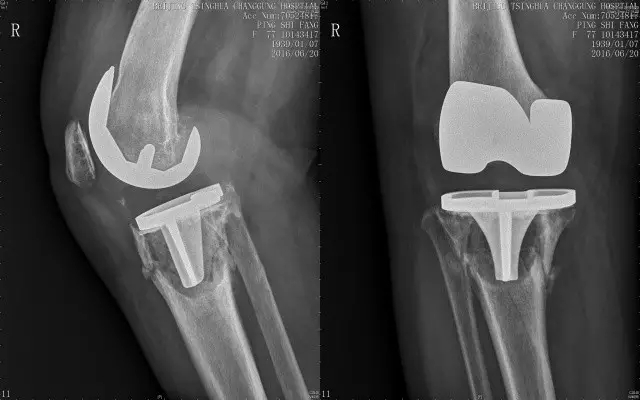

生活和工作方式的改变让越来越多的人患上慢性关节病,体重增加、运动缺乏和不良姿势是主要原因。慢性关节炎是致残性疾病中最常见的一种,晚期患者会面临关节畸形和关节功能丧失,这时候保守治疗基本上没什么效果,患者要考虑置换人工关节。近年来,人工关节置换术的手术量逐年上升,但仍有许多患者对其保持怀疑,尤其担心副作用,今天我们就来看看有哪些副作用!

人工关节置换术有哪些副作用?如何预防?

我们看到人工关节置换术的副作用并不少,可为什么选择人工关节置换术的人却越来越多呢?这是因为人工关节置换术,确实能给终末期的关节病患者带来巨大的帮助。

以类风湿关节炎晚期为例,关节畸形会明显影响关节的生理功能,甚至完全丧失关节活动能力,这个时候再怎么吃药也不能恢复关节的活动能力,当然要选择人工关节置换,比较置换人工关节的副作用风险,总没有长期卧床的危害大吧!置换人工关节后,患者的关节疼痛会大幅消除,关节活动度也会大幅恢复,可以从卧床不起,到恢复基本的日常活动能力,对病情的改善是显著的!

而且,随着医疗技术的进步,人工关节置换无论是假体寿命还是手术水平都有了大幅提高,手术的成功率是非常高的,大的并发症一般很少出现,在手术的安全性上患者其实不必过分担心。